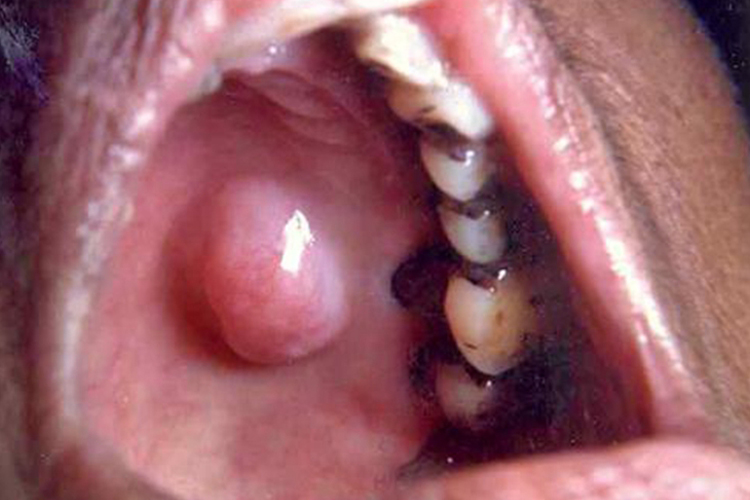

多形性腺瘤

多形性腺瘤可发生口腔上颚。肿瘤生长缓慢,常无自觉症状。肿瘤界限清楚,质地中等,扪诊呈结节状,一般可活动。当肿瘤在缓慢生长一段时期以后,突然出现生长加速,并伴有疼痛等症状时,多为恶变。